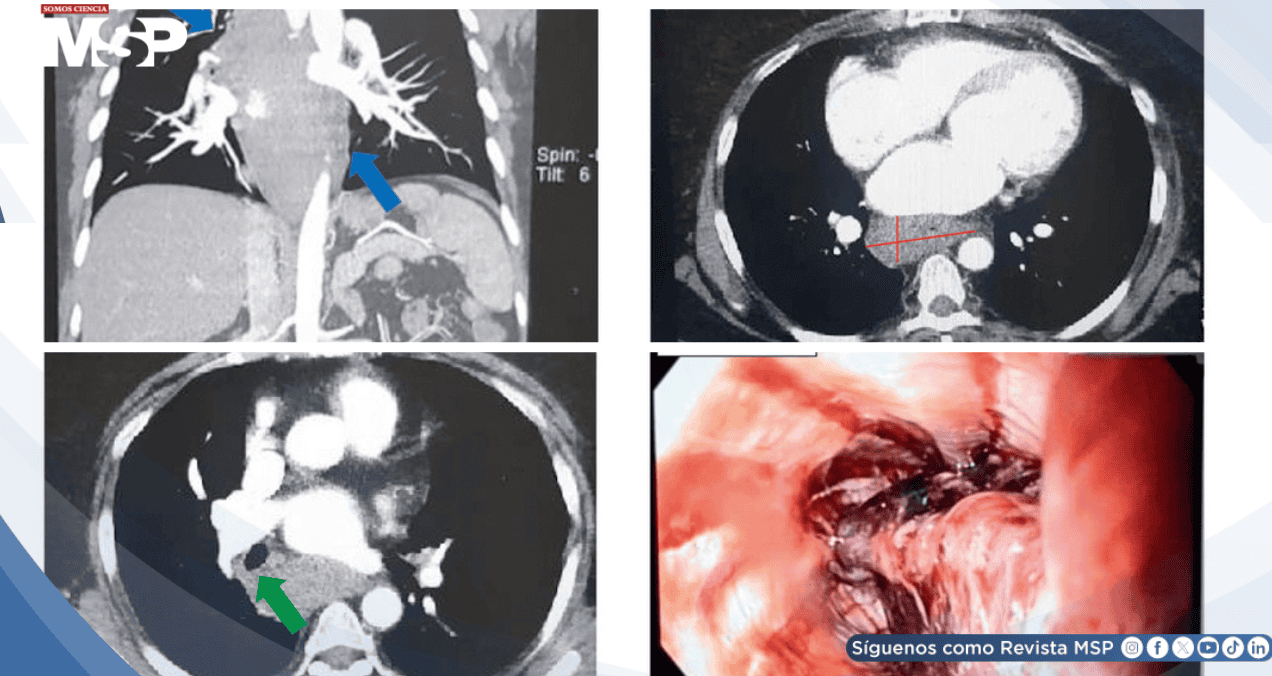

El electrocardiograma sin cambios isquémicos y las enzimas cardíacas normales descartaron infarto. La tomografía computarizada excluyó disección aórtica pero reveló una lesión de 52 mm en el margen esofágico y mediastino posterior.

A las 4 horas del ingreso, la paciente desarrolló odinofagia, disfagia y diaforesis fría, reorientando el diagnóstico hacia patología gastrointestinal superior. El estudio radiográfico con bario y la endoscopia gastrointestinal demostraron extensa hemorragia mural con formación de coágulos, confirmando el diagnóstico de hematoma esofágico intramural.

Los hallazgos imagenológicos son reveladores. La tomografía computarizada puede mostrar engrosamiento de pared esofágica, irregularidades y estrechamiento luminal. La endoscopia esofágica es el estándar de oro, demostrando claramente la presencia, extensión y complicaciones del hematoma.